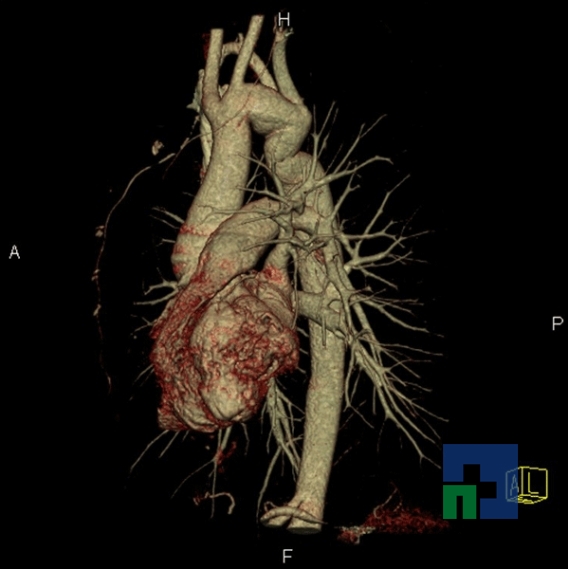

- Accidentelor vasculare cerebrale ischemice sau hemoragice

- Fistula carotido-cavernoasa